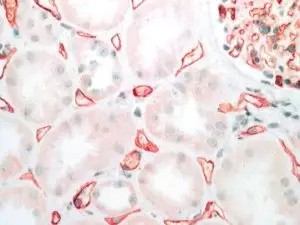

C4d Function Circulating alloantibodies encounter the grafted endothelium as the first target. Living endothelial cells can rapidly eliminate bound antibodies from the cell surface by “capping”, “shedding” or “internalisation”. C4d is the degradation product of the activated complement factor C4, a component of the classical complement cascade, which is typically initiated by binding of antibodies to specific target molecules. Detection of C4d is regarded as an indirect sign, a “footprint” of an antibody response against the allograft. The majority of publications describe C4d as an important biomarker in kidney transplantation but also in heart, liver, and other transplants.